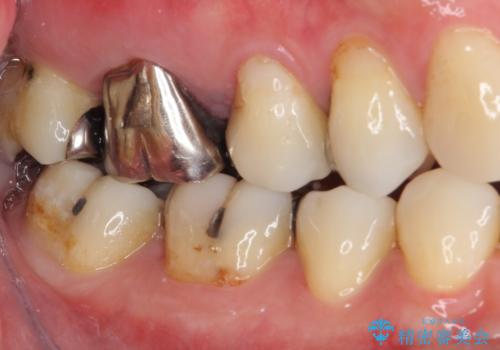

- 奥歯に強い痛みを感じるとのことで来院された患者様です。

診査したところ、既に根管治療されている大臼歯の咬合痛と、神経の残っている手前の小臼歯の強い冷熱痛を認めました。

小臼歯は根管治療後に痛みが引きましたが、隣の大臼歯の痛みは引かなかったため、大臼歯も根管治療を行いました。

根管治療後に痛みは引き、半年後のレントゲン写真では根尖の病変の消失が認められました。